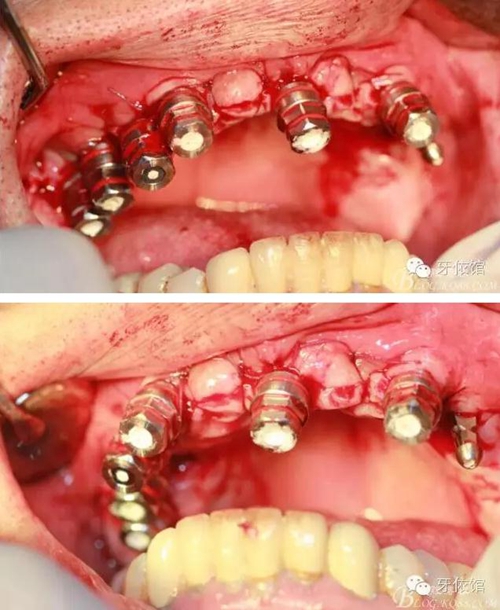

其余牙位也分別將植體植入

去除多余軟組織

將攜帶體重新與植體連接

將左側(cè)5(5個月前種的)連接轉(zhuǎn)移桿

縫合